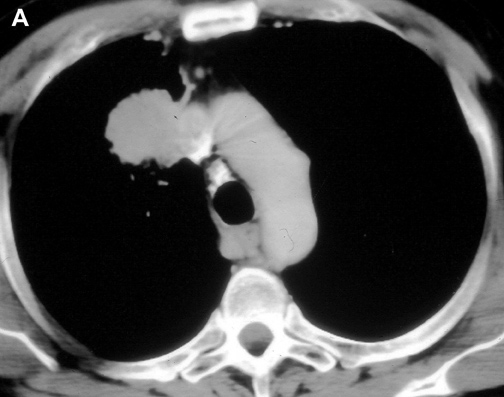

The anatomy of the SVC (Figure 1) and left brachiocephalic vein put this venous system in a critical area vulnerable to tumors arising both in the lung and anterior mediastinum. Malignant invasion is the most frequent indication for SVC resection and reconstruction. Lung cancer can involve the vessel with direct invasion by primary tumors arising in the right upper lobe or by nodal metastases (stations R2, R4 and 3) (Figure 2). Anterior mediastinal tumors (thymoma, thymic carcinoma, germ cell tumors, etc) may involve directly both the SVC and the left brachiocephalic vein (Figure 3). Primary tumors of the SVC represent a rare indication for surgery. Other infrequent indications are saccular aneurysms or primary malformations and traumatic lesions (iatrogenic, blunt, or penetrating injuries).

Figure 2A Figure 2B Figure 3

Figure 2A & B. (A) Lung cancer invading the superior vena cava. (B) Mediastinal lymph nodes invading the superior vena cava. Figure 3. Cortical thymoma invading the superior vena cava.